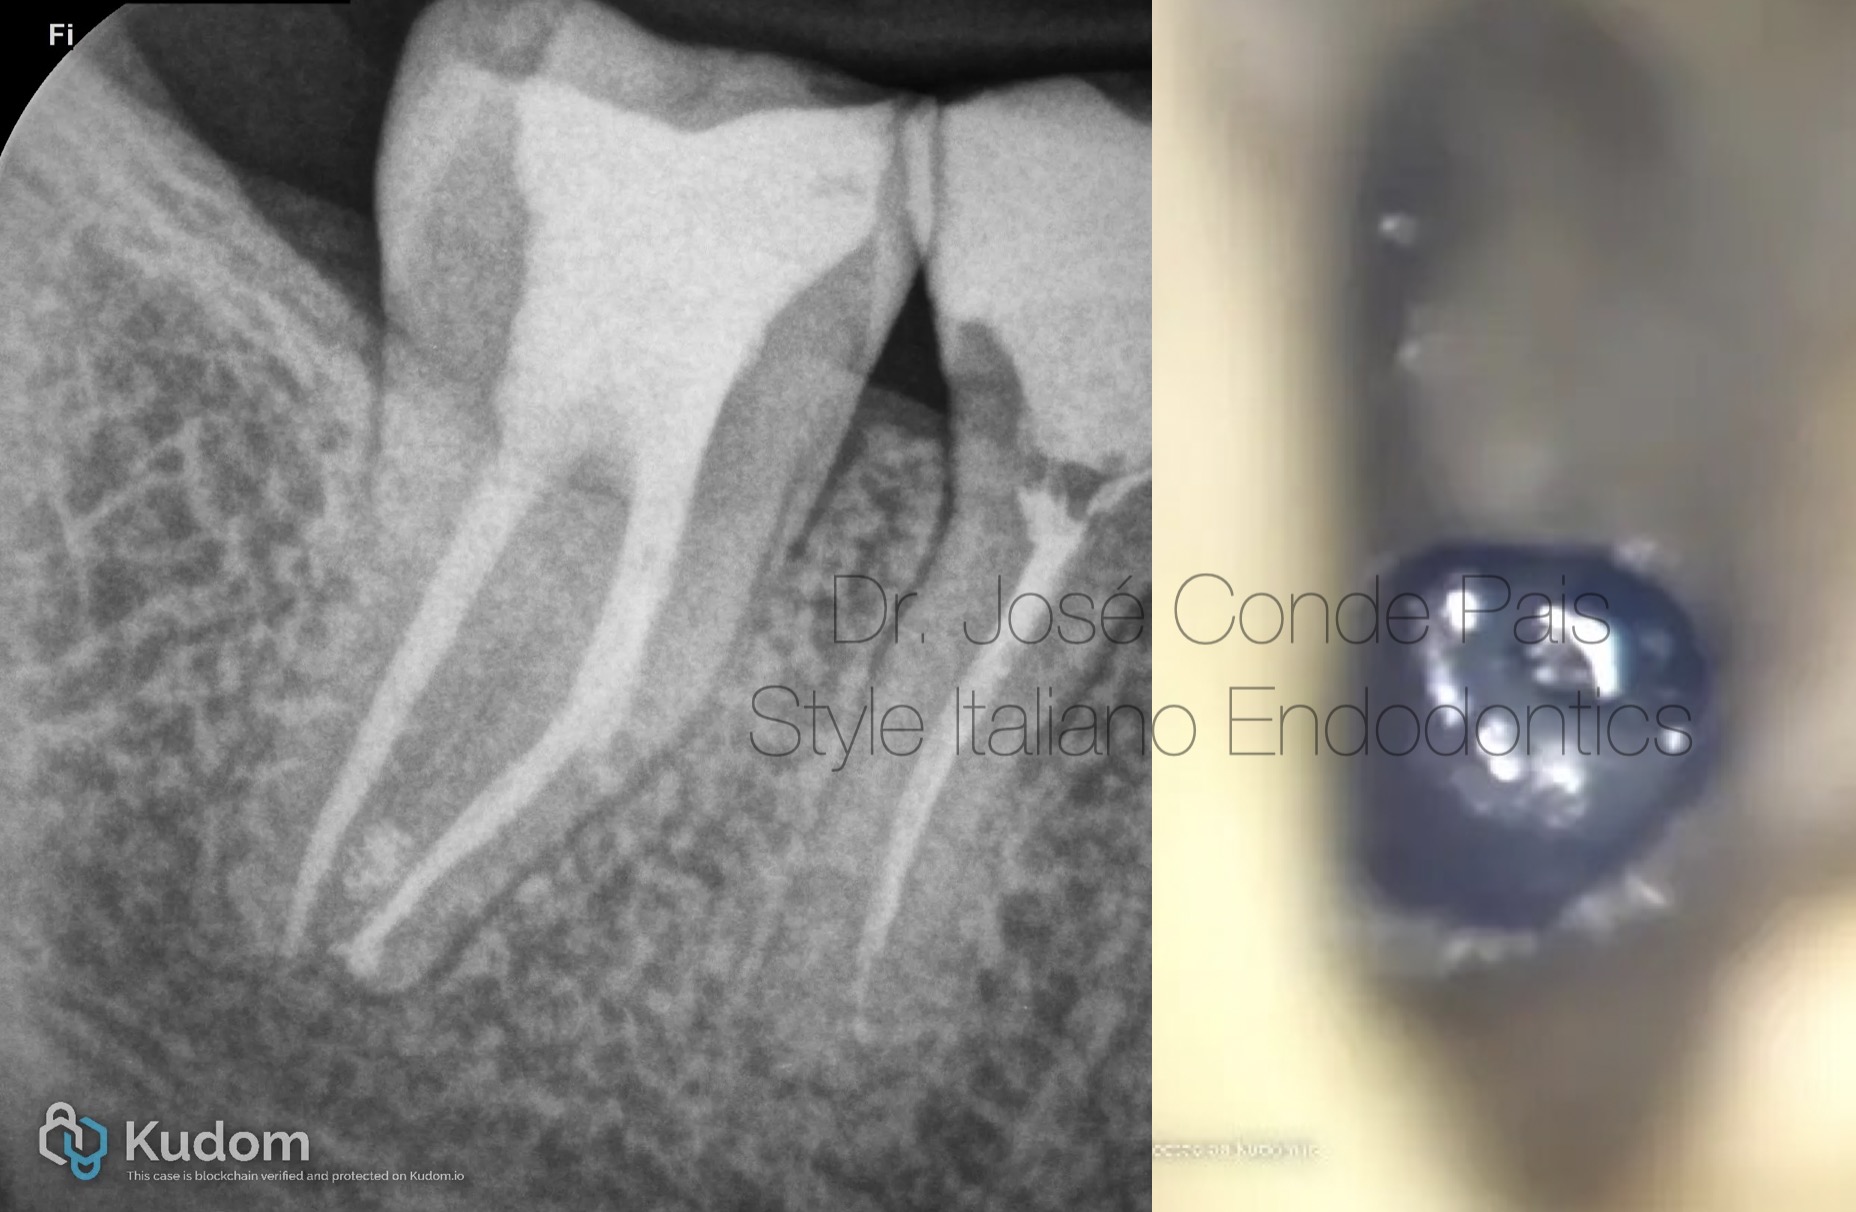

Transforming a Non-Visible Separated File into a Visible Fragment: A Conservative Retrieval Approach

Retreatments Separated instruments

Instrument separation is a well-recognized complication in endodontic practice, and its management can significantly influence the long-term prognosis of the tooth. While some fractured instruments are readily visible and accessible, others remain hidden, particularly when located beyond canal curvatures. Non-visible fragments pose a greater challenge, as blind retrieval attempts risk excessive dentin removal, perforation, or structural weakening of the root.